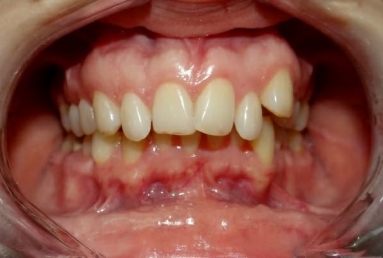

SAPPHIRE ORTHODONTIC DEVICE